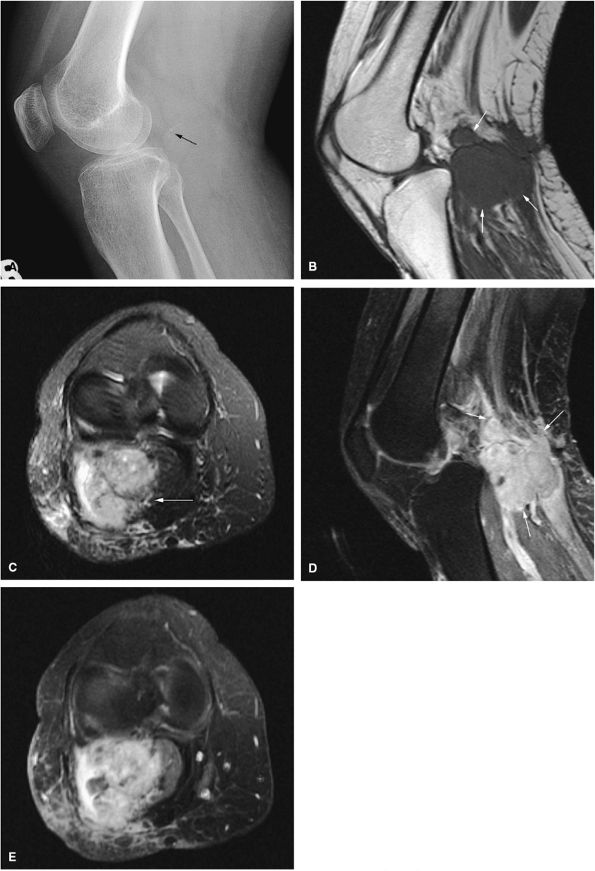

FIGURE 14-34 ● Extensive marrow edema (arrowheads) in reaction to an epiphyseal-based chondroblastoma of the tibia (arrows) demonstrates low signal intensity on a coronal T1-weighted image (A) and hyperintensity on a coronal STIR image (B). Axial STIR image (C) demonstrates fluid–fluid levels within the lesions (arrow). (D) A coronal CT image shows a well-defined lytic defect in the tibial plateau (arrow). (E) An axial CT image obtained during radiofrequency ablation of the tumor shows the radiofrequency probe (arrow) within the chondroblastoma.

-

Epiphyseal and metaphyseal marrow edema associated with periosteal reaction is a frequent finding, seen in up to 57% of cases of long-bone involvement.67 MR imaging is sensitive to this extensive reactive marrow edema, which demonstrates decreased signal intensity on T1-weighted images and increased signal intensity on T2-weighted or STIR images.

Fluid–fluid levels can be seen in chondroblastomas.53

T2-weighted images are useful in demonstrating the lobular chondroid internal architecture and fine lobular margins of the lesion.68